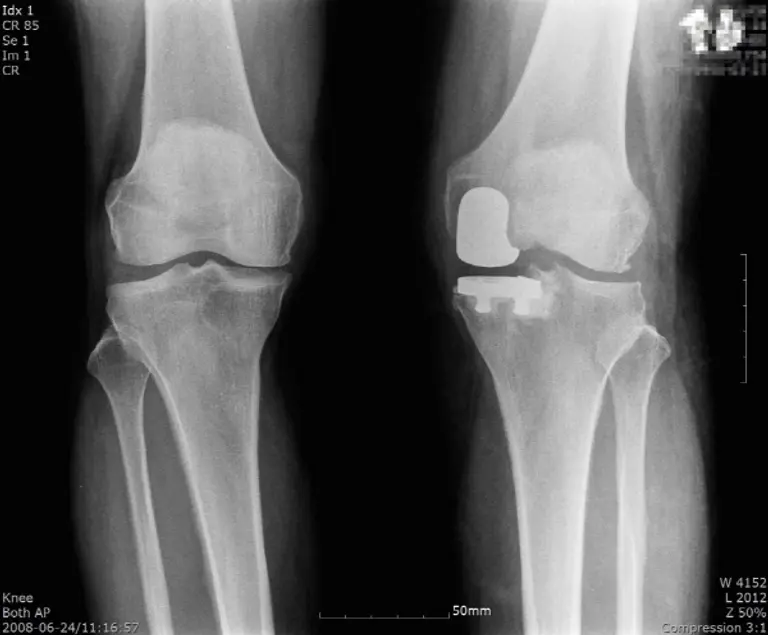

세계적 학술지인 ‘더 니(The Knee)에 게재된 ‘인공슬관절 부분치환술의 생체 역학적 결과에 대퇴골 구조물의 위치가 미치는 영향’ 논문에 따르면 부분치환술 진행 시 구조물 위치에 따라 치료의 결과가 달라질 수 있다.

무릎 관절을 구성하는 구조물들의 위치는 관절의 기능을 결정하는 중요한 역할을 하는데, 대퇴골 중심에서 내측 및 외측으로 각각 3mm, 5mm 이동된 5개 모델을 보행 하중 조건에서 분석하면 대퇴골 끝부분의 중심에 부분인공관절을 삽입할수록 개선 효과가 높아진다.

연세사랑병원 서동석 원장(연세사랑병원 인공관절팀)은 “부분 인공관절 수술은 내측 인대의 기능이 정상이고 무릎 관절의 굴곡이 90도 이상이어야 고려해볼 수 있다. 정밀한 검사를 통해 정확한 인공관절 삽입위치를 확인해야 하므로 의료진의 임상 경험이 매우 중요하다”며 “수술 후에는 인공관절 수명 연장과 관절염 예방을 위해 규칙적인 운동으로 관절 주변 근육을 강화해줄 것을 권장한다”고 조언했다.